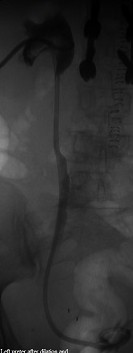

Distal left ureter after dilation and nephroureteral catheterization

Published July 12, 2014 at 133 × 353 in Bilateral insertion of nephroureteral stents after balloon dilation of malignant obstruction of the distal ureters. Ken U. Ekechukwu, MD, MPH, FACP..

Distal left ureter after stenting.